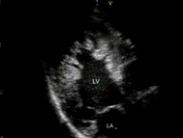

心室肌致密化不全(non-compaction of ventricular myocardium,NVM)是胚胎初期心內(nèi)膜心肌的形態(tài)學(xué)發(fā)生受到限制,使發(fā)展中的肌小梁不能致密化導(dǎo)致心室發(fā)育不全,屬罕見(jiàn)的先天性心肌病。